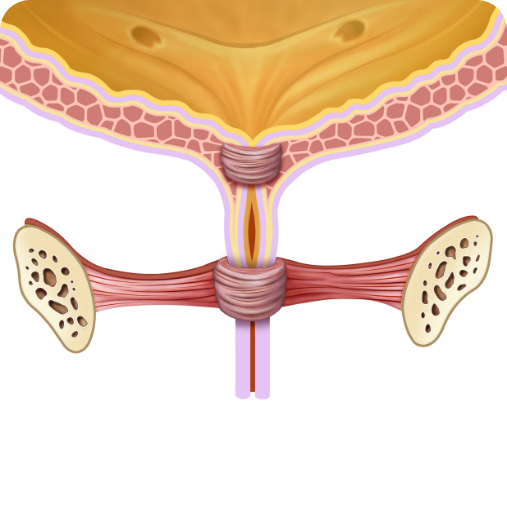

PŘED kúrou:

Slabé svaly močové trubice

PO kúře:

Silné svaly močové trubice